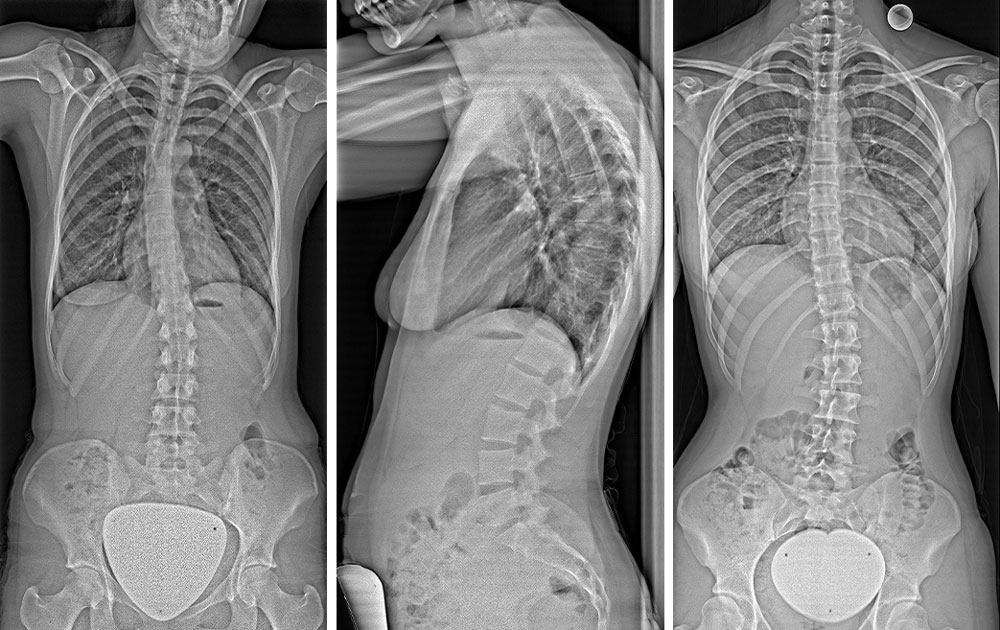

The Rax’s ability to perform weight-bearing imaging of the spine while standing is crucial. (See True2scale Body Scan image below.) This method provides a more accurate representation of joint biomechanics compared to traditional supine imaging like MRI and CT. Upright imaging offers a more accurate depiction of spine pathology as well, making it more effective for diagnosis and treatment planning. This approach could lead to improved prosthesis selection or surgery planning for patients with pain in weight-bearing positions.2

Images using True2scale Body Scan on the Rax for supine and standing imaging in a scoliosis patient.

Additional tools commonly used in diagnostic radiography specific to orthopedics include stitching and slot scanning. Orthopedic stitching software combines multiple overlapping X-ray images into one full-length view of the spine or lower limbs, assessing alignment, limb length and deformities. Slot scanning enhances orthopedic imaging accuracy by capturing a continuous, distortion- free image. Its narrow, collimated X-ray beam preserves true anatomical proportions, while reduced scatter radiation improves sharpness and contrast.3,4 These features ensure highly reproducible measurements for scoliosis, limb alignment and surgical planning.